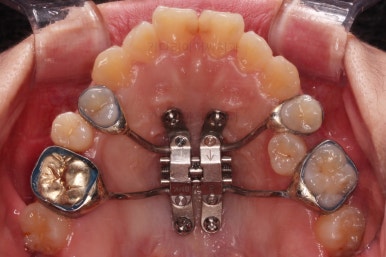

이번 부산교정 환자분은 교정치료 첫 단꼐로 악궁확장장치를 했는데요.

일반 확장 장치로는 불가하다는 판단이 되어 미니스크류를 활용한 악궁확장장치(MARPE)를 해주었어요.

저희 부산교정 키다리아저씨치과에서는 수십가지 분석을 통해 악궁확장이 정말 필요한지 아닌지를 판단하며 더하기 해서 일반 악궁확장장치(RPE)로 가능한지, 미니스크류를 이용한 악궁확장장치(MARPE)를 써야하는지 구분하여 치료를 하고 있습니다.

간혹 나이로만 구분하여 성인은 무조건 MARPE, 청소년은 RPE 이렇게 치료를 하는 경우도 있는데 맞지 않습니다.

성인도 일반 악궁확장장치가 가능한 경우가 많아요.

이번 환자분은 일반 악궁확장장치로는 불가하다는 판단에 미니스크류를 이용한 악궁확장을 시행했고요.

입천장에 장치를 3개월 가량 유지하는 동안 치아에 브라켓을 부착하여 가지런하게 해줍니다.